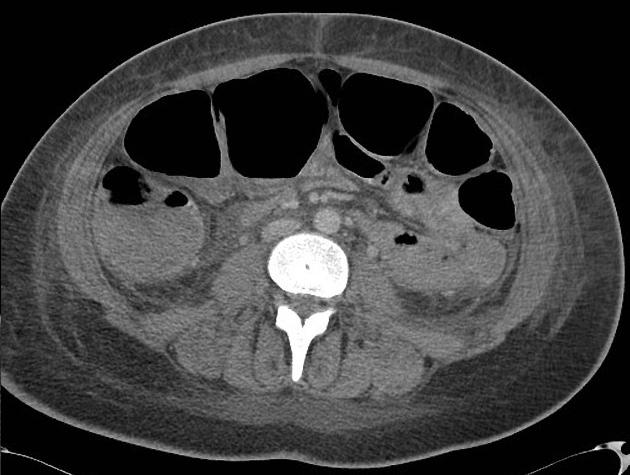

Toxic megacolon dans

maladie de Crohn . Image de distension du colon

transverse avec image de stenose inflamatoire et

epaissisement du colon sigmoigienne . Image

radiologique TDM en coupe coronale |

Meme cas en

coupe coronal a traver la colon transverse

. Maladie |